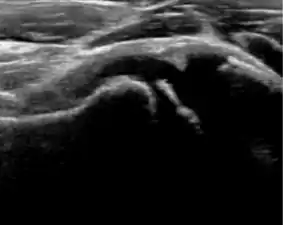

Ultrasound

Ultrasound is the first-choice technique for diagnosis of newborns hip dysplasia. In experienced hands with appropriate technology, ultrasound can also be useful during the first year of life. Some European healthcare systems encourage universal ultrasound screening in neonates between the sixth and eighth weeks. Although it shows higher initial costs caused, it leads to significant reduction in the total number and overall costs of dysplastic hips undergoing operative and nonoperative treatment.[1]

Ultrasound allows categorizing pediatric hips, according to Graf’s criteria, in four main types: normal, immature, and dysplastic (subluxed and dislocated). This classification is based on measurements of the acetabular inclination angle (alpha), cartilage roof angle (beta), and infant age. The femoral head coverage can also be determined by dividing the length of the femoral head covered by the acetabular fossa and the diameter of the femoral head. Its lower normal limits are 47% for boys and 44% for girls (Figure 11).[1]

During childhood, ultrasound is a quick method to assess hip pain and quite often may be used to avoid use of irradiating techniques, such as radiography or CT. Ultrasound allows evaluation of joint effusion, synovial thickening and neovascularity, the bone/cartilage contour, and the femoral head-neck alignment. Although sonography is extremely sensitive in detecting increased synovial fluid, it is nonspecific and cannot be used with accuracy to determine the type of fluid. Transient synovitis of the hip, despite being the most frequent cause of pain in children between 3 and 10 years, remains a diagnosis of exclusion. It usually shows anechoic fluid, but echogenic fluid can also be found. The effusion is considered pathologic when it is measured at >2 mm in thickness. The differential diagnosis is wide, including osteomyelitis, septic arthritis, primary or metastatic lesions, LCPD, and SCFE. Discrimination from septic arthritis is challenging, often requiring joint aspiration. In septic arthritis, US is able to demonstrate a hip joint effusion, synovial thickening, and cartilage damage, although the appearances are nonspecific.[1]

A step between the head and the physis can be detected in children with SCFE, while abnormalities in the femoral head contour may suggest the presence of LCPD. In both cases, radiographs are mandatory to confirm diagnosis and severity (Figure 12).[1]

In adults, the most common application for US is to detect tendon or muscle injuries, effusion or synovitis within the hip joint or its adjacent bursae. Joint effusions may be due to many intra-articular processes and this may need another imaging technique to achieve a specific diagnosis.[1]